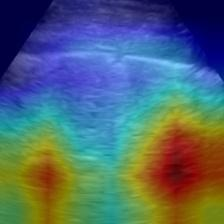

Most deep neural networks (DNNs) based ultrasound (US) medical image analysis models use pretrained backbones (e.g., ImageNet) for better model generalization. However, the domain gap between natural and medical images causes an inevitable performance bottleneck. To alleviate this problem, an US dataset named US-4 is constructed for direct pretraining on the same domain. It contains over 23,000 images from four US video sub-datasets. To learn robust features from US-4, we propose an US semi-supervised contrastive learning method, named USCL, for pretraining. In order to avoid high similarities between negative pairs as well as mine abundant visual features from limited US videos, USCL adopts a sample pair generation method to enrich the feature involved in a single step of contrastive optimization. Extensive experiments on several downstream tasks show the superiority of USCL pretraining against ImageNet pretraining and other state-of-the-art (SOTA) pretraining approaches. In particular, USCL pretrained backbone achieves fine-tuning accuracy of over 94% on POCUS dataset, which is 10% higher than 84% of the ImageNet pretrained model. The source codes of this work are available at https://github.com/983632847/USCL.